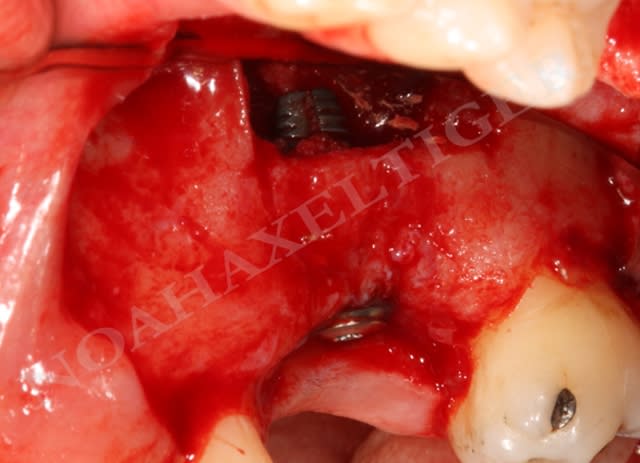

cas clinique avec abord transantral:

Comme il a été mentionné plus haut, la racine palatine des molaires maxillaires pose un problème spécial pendant les procédures de chirurgie endodontique.

Ces racines sont 50% plus près du sinus qu'elles sont du palais (Wallace 1996), montrent une communication apicale avec le sinus dans 20% du temps et sont à moins de 0.5 millimètre du sinus dans 40% du temps (Watzek 1997).

Un palais profond offre de longs murs latéraux verticaux et un accès amélioré palatin. Un palais peu profond présente non seulement des difficultés de visibilité et d'incision mais l'accès palatin est compliqué par la proximité apex/vaisseaux palatins.

Pour ces raisons l'approche transantrale peut être vue comme une option souhaitable. Cette technique a été décrite et avec succès employée par plusieurs auteurs (Altonen 1975, Wallace 1996 - désolé pour la biblio ancienne mais ce sont des articles de références).

Le protocole est le même que lors d’un sinuslift avec pour seule différence la taille plus importante du volet d’accès osseux. L’utilisation du piezo permet une découpe sure et une conservation du volet osseux qui pourra en fin de chirurgie être replacé.

L’élevation de la membrane sinusienne est pratiquée en profondeur jusqu’à atteindre la proéminence de la racine palatine. La suite de l’intervention est pratiquée sous microscope opératoire : la mince couche osseuse recouvrant l’apex palatin est retirée avec un ciseau à os. La racine est réséquée au niveau désiré, l'extrémité de la racine est préparée avec un rétrotip ultrasonique selon les principes de la chirurgie endodontique apicale. L’obturation à rétro se fait avec du MTA.

Une technique appropriée, une manipulation soigneuse du tissu et le recours à des antibiotiques recommandés permettent de réduire au minimum les complications.